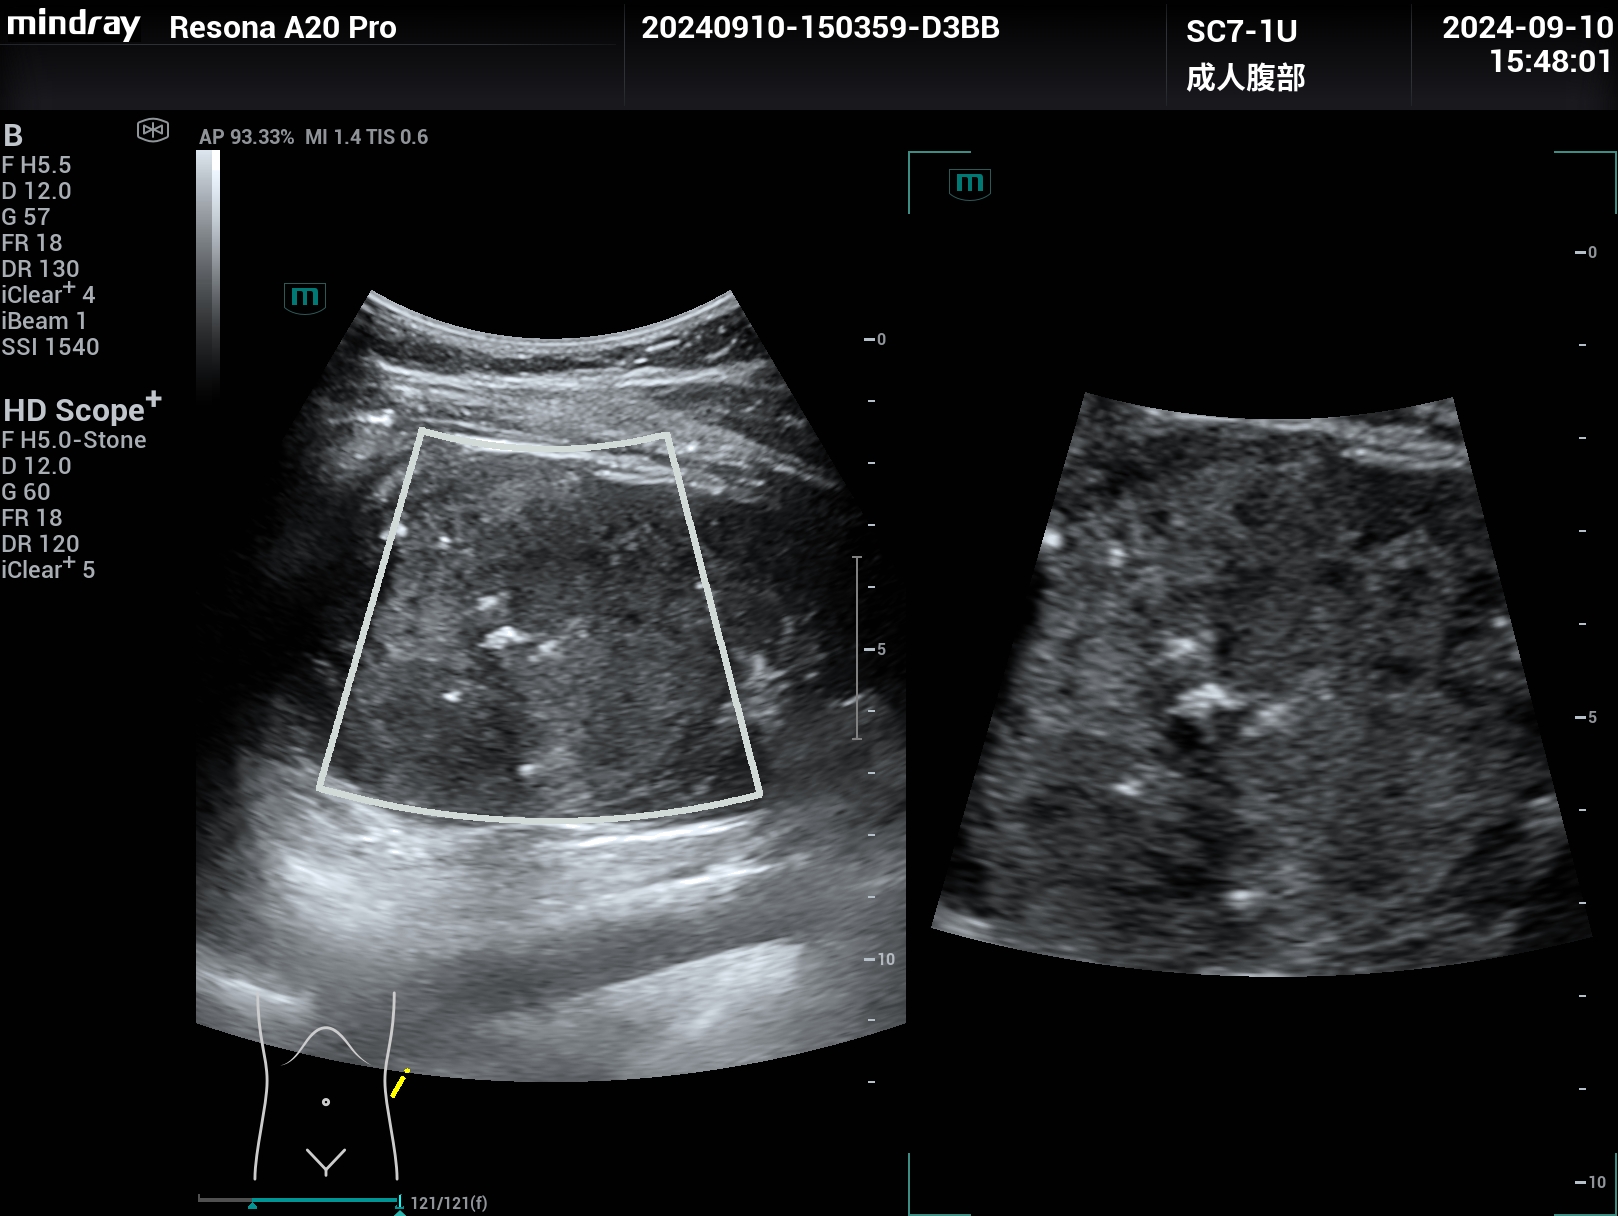

肾脏癌性大包块,扩展成像,腹部探头变成腔内探头的超宽视野,但分辨力依然清晰,超高端Resona A20

肾脏癌性大包块,腹部探头扩展成像,腹部探头成腔内探头的超宽视野,但分辨力依然清晰。